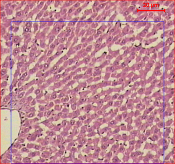

Effect of pioglitazone, Monascus purpureus (MP) and their combination on hepatic and pancreatic histology

Gross examination of liver showed no abnormalities. The microscopic examination of sections of liver from control group showed preserved hepatic architecture with normal hepatocytes. Sections of liver tissue of STZ-treated rats showed normal hepatic architecture with focal inflammatory cellular infiltrate and focal hepatocytic degeneration. Sections of liver treated with Pio (10 mg/kg) showed moderate degeneration of hepatocytes with mild cellular infiltrate. Sections of liver tissue treated with MP (500 mg/kg) treated rats showed moderate hepatic infiltration by inflammatory cells. Liver tissue of the group treated with Pio (10 mg/kg) in combination with MP (250 mg/kg) showed mild focal degeneration of hepatocytes.

Fig. 10: Photomicrograph of Pio, MP and Pio+MP on liver in STZ-treated diabetic rats. STZ: streptozocin Pio: pioglitazone, MP: Monascus purpureus. [mean±SEM, n= 6] significant, * when compared to normal and @ P<0.05 when compared to control diabetic

A-Section in control liver tissue showing preserved hepatic architecture with normal hepatocytes (H and E, X100). B-Section in normal pancreatic tissue, the islets show intact Beta cells (H and E, X100). C-Normal pancreatic tissue section with overlapped binary image showing a mean islet area 1278.26 square micrometer. D-Section of liver tissue from STZ treated rat showing normal hepatic architecture with focal inflammatory cell infiltrates with focal hepatocytic degeneration (H and E, X100). E-STZ pancreatic tissue section, the islets show degenerated Beta cells with peripheral lymphocytic infiltrate (H and E, X100). F-Pancreatic sections from STZ treated rat with overlapped binary image showing a mean islet area 785.42 square micrometer. J-Section of liver tissue from Pio treated rat showing moderate degeneration of hepatocytes with mild cellular infiltrate (H and E, X100). K-Pio treated pancreatic tissue section showed that the islets have few Beta cells (H and E, X100). L-Pancreatic sections from Pio treated rat with mean islet area 549.28 square micrometer. M-Section of liver tissue from Stat treated rat showing moderate hepatic infiltration by inflammatory cells (H and E, X100). N-Stat treated pancreatic tissue section showed that the islets had decreased number of Beta cells (H and E, X100). O-Pancreatic sections from Stat treated rat with mean islet area 724.11 square micrometer. P-Section of liver tissue from PS treated rat showing focal degeneration of hepatocytes (H and E, X100). Q-PS treated pancreatic tissue section; the islets show decreased number of Beta cells with peripheral inflammatory cellular infiltrate (H and E, X100). R-Pancreatic sections from PS treated rat with mean islet area 659.89 square micrometer.